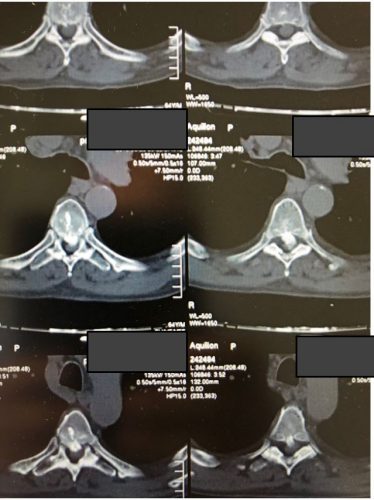

Ο απεικονιστικός έλεγχος ανέδειξε δύο επασβεστωμένες θωρακικές δισκοκήλες στο ύψος Θ6/7 και Θ7/8.